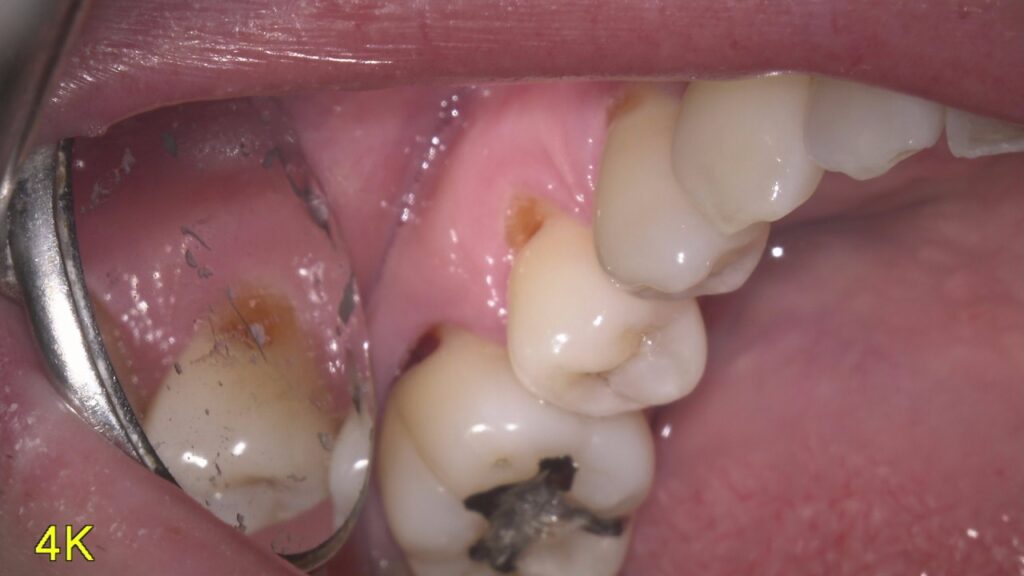

むし歯の再発 (二次う蝕)とは

過去に治療を行った部位に再度発生した虫歯です。主な原因としては「詰め物の劣化」「治療後の口腔ケア不足」「最初の治療精度が低かったため」などがあります。

◆ 詰め物の劣化

虫歯治療に使用した詰め物・被せ物などが劣化した際にできる隙間や段差から虫歯菌が入り込み、虫歯になることがあります。特に銀歯は金属でできているため、熱が加わると膨張し、冷えると収縮するという特徴があります。普段の食生活で膨張と収縮が繰り返されることにより、接着面に隙間や段差ができます。銀歯だと必ず再発虫歯になるわけではありませんが、定期的な検診でリスクを抑えていきましょう。

◆ 最初の治療精度が低かった

治療時に完全に虫歯が除去できていなかった場合、残った細菌によって虫歯が再発する可能性が高まります。詰め物や被せ物を隙間なく接着できていない場合も同じです。当院ではこのようなことがないように細心の注意を払って治療をしております。定期的な検診をすることで予後の確認もできますので、ぜひお気軽にご来院ください。